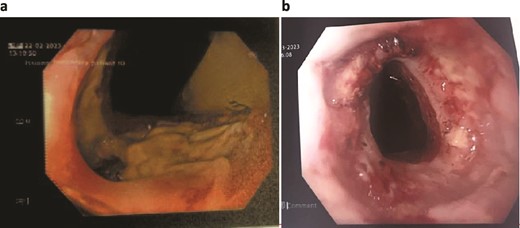

The patient was treated with antibiotics and VACStent insertions, requiring two stent placements (Fig. 1a). By the second stent removal, the anastomotic leak had closed (Fig. 1b). He experienced an episode of acute kidney injury managed with fluids. By postoperative day 24, the leak had resolved, the stent and porta Cath were removed, and the patient was discharged with normal blood results and a follow-up scheduled. The patient continued to manage his overall health with regular follow-ups.

Patient One: (a) Before VACStent insertion, showing the oesophageal defect. (b) After VACStent treatment, demonstrating successful defect closure.